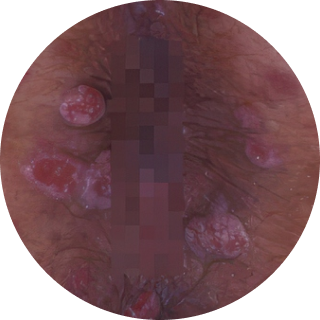

무증상인 경우도 많습니다. 여러 개가 다발로 생기고,

닭벼슬이나 양배추처럼 보기 불편한 모양을 띠기도 합니다.

양배추모양 (닭벼슬)

양배추모양 (닭벼슬) 작은 구진모양

작은 구진모양 물집 형태

물집 형태 편평사마귀

편평사마귀